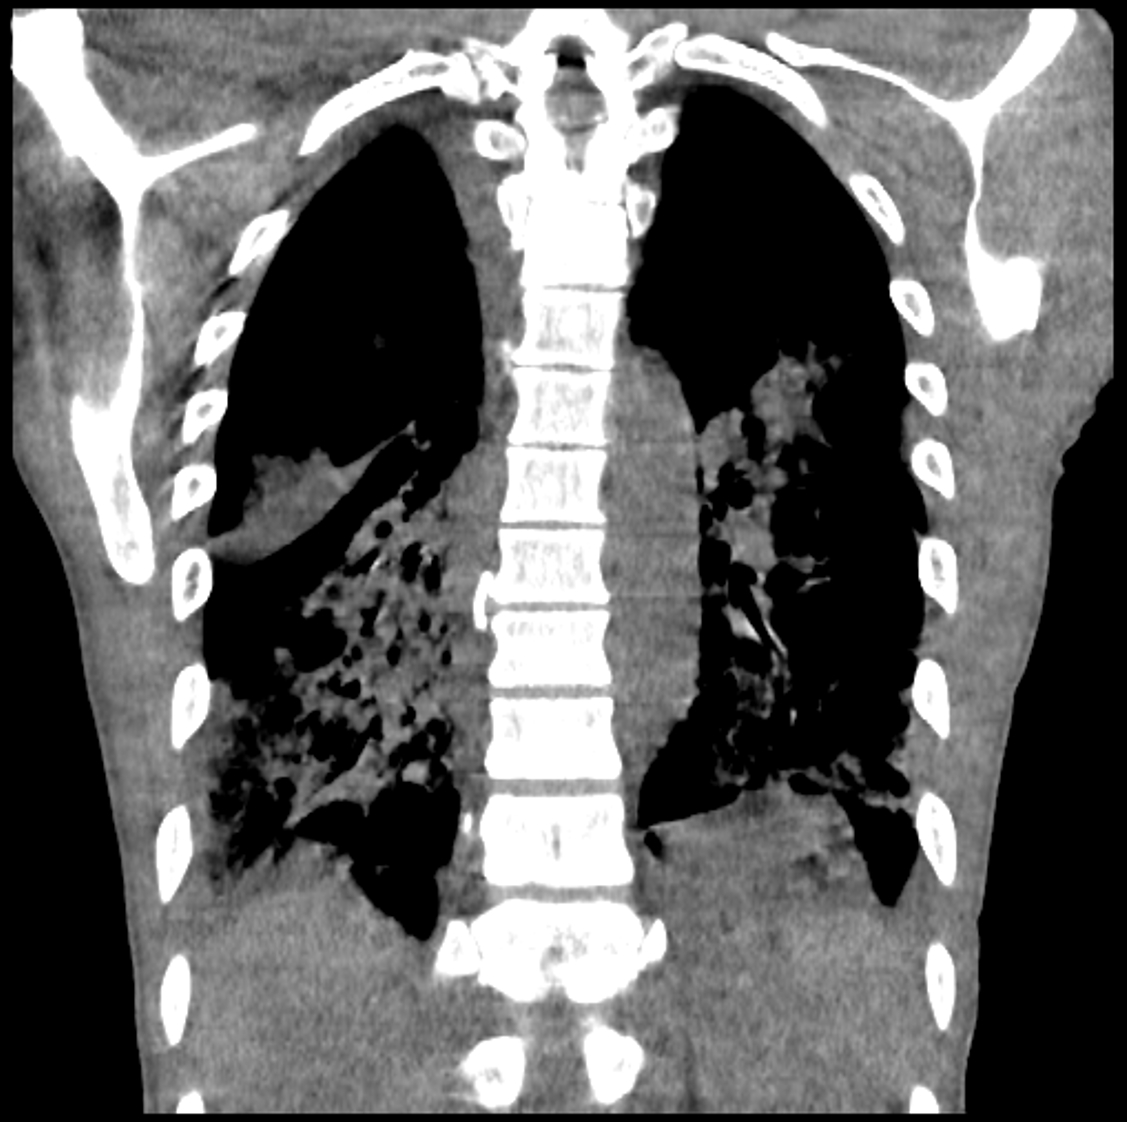

A 47-year-old male with supposed history of rheumatoid arthritis (RA) presented with shortness of breath and had a cardiac arrest in the ED. He was found to have an ejection fraction of 10-15%. Ischemic evaluation and genetic testing were negative. Dermatologic findings of the Gottron sign, heliotrope rash, shawl sign, and mechanic’s hands were noted along with crackles in his lungs. Inflammatory markers were elevated but creatine kinase (CK) and aldolase were normal. Rheumatoid factor, anti-CCP, and anti-Jo-1 antibodies were negative. Myositis panel revealed high positive MDA-5 antibodies. Lung biopsy revealed ILD and endomyocardial biopsy showed evidence of inflammation. He was treated with steroids and intravenous immunoglobulin with inotropic support.

Anti-MDA5 dermatomyositis is known to be associated with high mortality related to rapidly progressive ILD. In contrast, this patient’s course was dominated by myocardial disease. Cardiac involvement in clinically apparent in only 10-20% of patients, and myocardial inflammation can lead to complications with poor outcomes. Furthermore, the lack of classic weakness and normal CK and aldolase posed a diagnostic challenge. Early diagnosis and initiation of anti-inflammatory therapy is essential to mitigate the high mortality rates associated with this elusive disease.